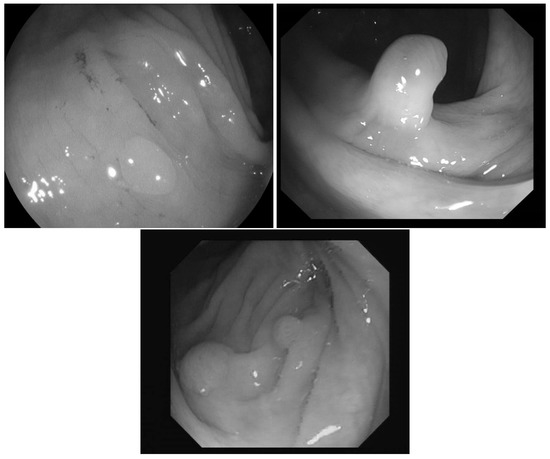

In [23] the images were classified into three classes based on the angle of the view of the polyp: zenithal, lateral, and semilateral, see Figure 1. In the zenital case, the polyps can be seen in a top view, from this view they are not significantly lighter than the environment, but their circumference and the surface texture are usually well distinguishable. A polyp when viewed from its side (i.e., from a lateral view) with a much darker–distant and therefore, worse lit–bowel wall background. Then there is also an intermediate semilateral view. In this case, the background is somewhat darker than the polyp but often the contour, especially at the polyp’s base’ is hardly visible.

Figure 1. Sample pictures from widely used colorectal image-bases [13,23,24]. The left image shows the zenithal view of a colorectal polyp, the second one is a lateral view, while the third is a semilateral view. The resolution differences of the three databases are also visible on the images.